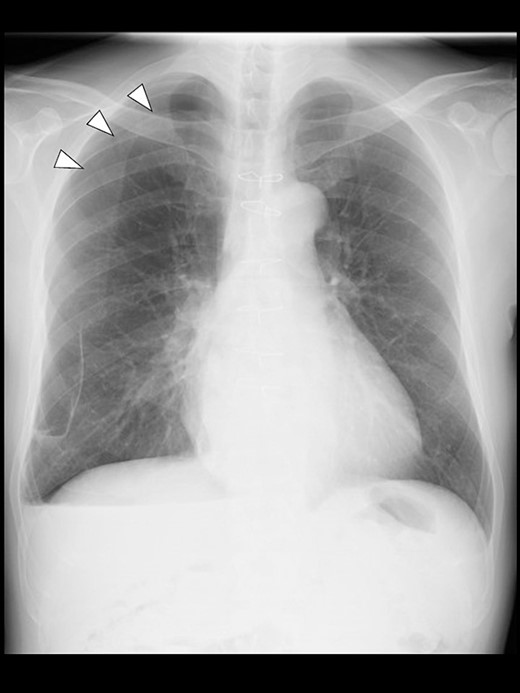

Even though the patient did not receive supplemental oxygen in the ward, SpO2 remained at 98%. Chest radiographs were not taken on the day of surgery. However, a chest radiograph taken in the upright position on postoperative Day (POD) 1 revealed a pneumothorax on the right side (Fig. 2), although he had no respiratory symptoms. Radiographs on PODs 2 and 3 revealed the pneumothorax remaining unchanged (Fig. 3). The patient was discharged from the hospital on POD 3 without any respiratory symptoms. A chest radiograph taken on POD 19 showed no remaining pneumothorax.

A chest radiograph in the upright position on POD 1 showing a right pneumothorax (arrowheads).